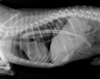

For the past 8 years, Veterinary Practice News has had an annual x-ray contest for the craziest things pet's have eaten. Here are the winners for 2013.